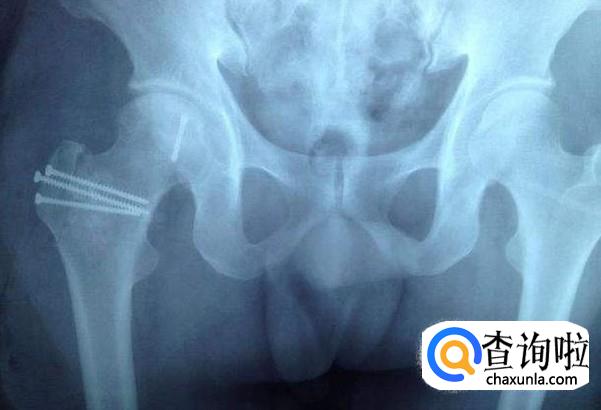

股骨头有两根,具体位置在骨盆下方,骨盆左右各有一个髋臼,两个股骨头和髋臼配合,共同起到支撑上体的作用。肱骨对人体非常重要,但也是人体最容易受伤的部位。

肱骨头是人体最重要的骨头,人坐立、行走都需要肱骨头的支撑作用,如果肱骨头受伤,人的行动能力会受到非常大的影响。

肱骨头最常见的疾病就是肱骨头坏死,又称无菌性股骨头坏死。发病原因是肱骨头供血不足,进而导致肱骨头骨质坏死。

股骨头的血供少。股骨头的血供主要依靠囊外动脉环发出的外侧支持带和内侧支持带动脉,血管的吻合支量少且薄弱,当一支血管被阻断而另一支不能及时代偿时,即会造成股骨头的供血障碍。

大致股骨头坏死可分为创伤性和非创伤性两大类,前者主要是由股骨颈骨折、髋关节脱位等髋部外伤引起,后者在我国的主要原因为酗酒、激素、先天因素等造成。